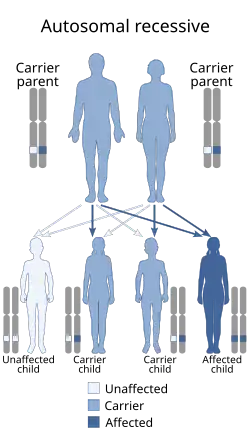

Около 2 % всех случаев ДЦП наследуются по аутосомно-рецессивному типу, причём глутаматдекарбоксилаза-1 (известная как GAD67 или GAD1) является одним из возможных вовлечённых ферментов[24].